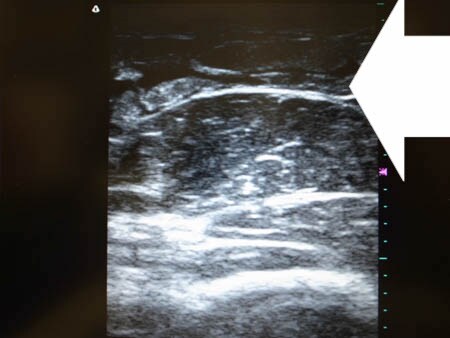

いつものように3Dタッチビュー(超音波)で

皮下脂肪層を評価してみましょう。

右二の腕

↓ ↓ ↓

上の画像の部分の皮下脂肪層をつまんでみましょう。

上の写真を見ればわかると思いますが

手術直前の皮下脂肪層はしっかりと厚みがありますが 手術直後の皮下脂肪層はほとんどありません。 確実に根こそいだ証ですね。